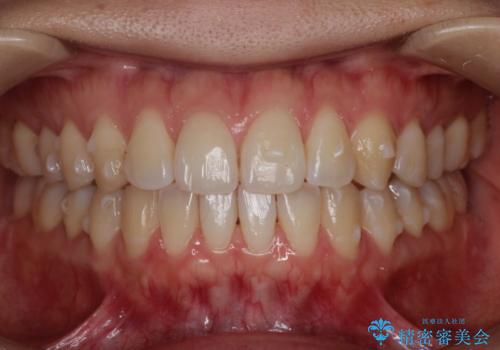

初診時の歯並びの状態としては、上下ともに前歯部に限局した軽度ののがたつき(叢生)がある状態でした。

主に歯列弓の拡大とディスキング(歯と歯の間に隙間を作る処置)を行い叢生を改善しました。

見た目、嚙み合わせ及び、治療期間や施術内容に大変ご満足いただきました。